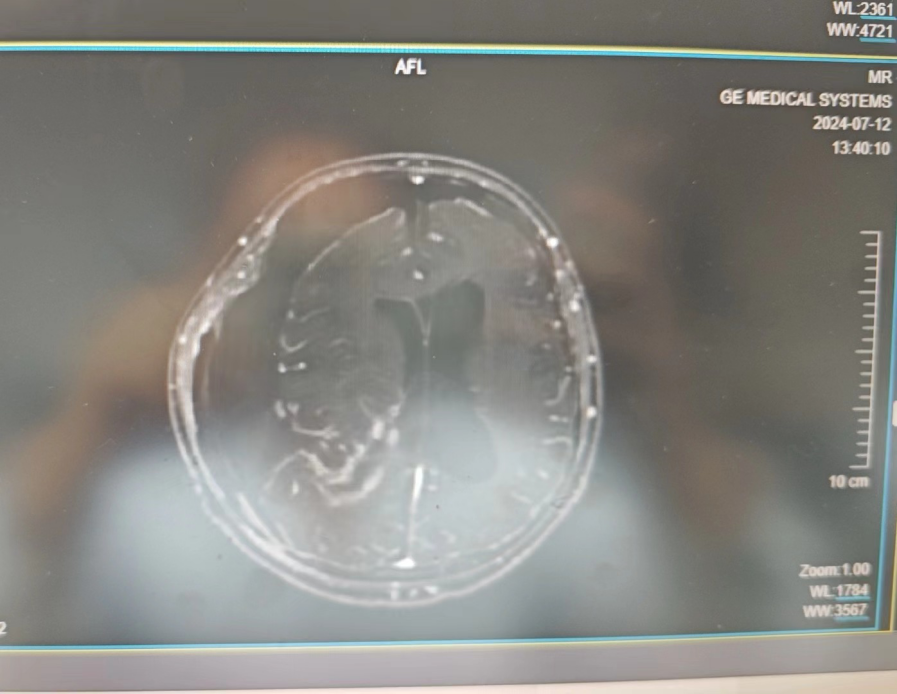

入院后行头部增强核磁共振提示:右侧额颞顶枕叶见范围约8.2*10.6*9.9cm混杂信号肿块影。如此巨大肿瘤,如不及时进行手术,患者将面临瘫痪甚至是死亡的危险。因此,医护人员为患者积极完善各种术前检查,并安排于7月4日上午进行手术。

(术后复查头部增强核磁共振)